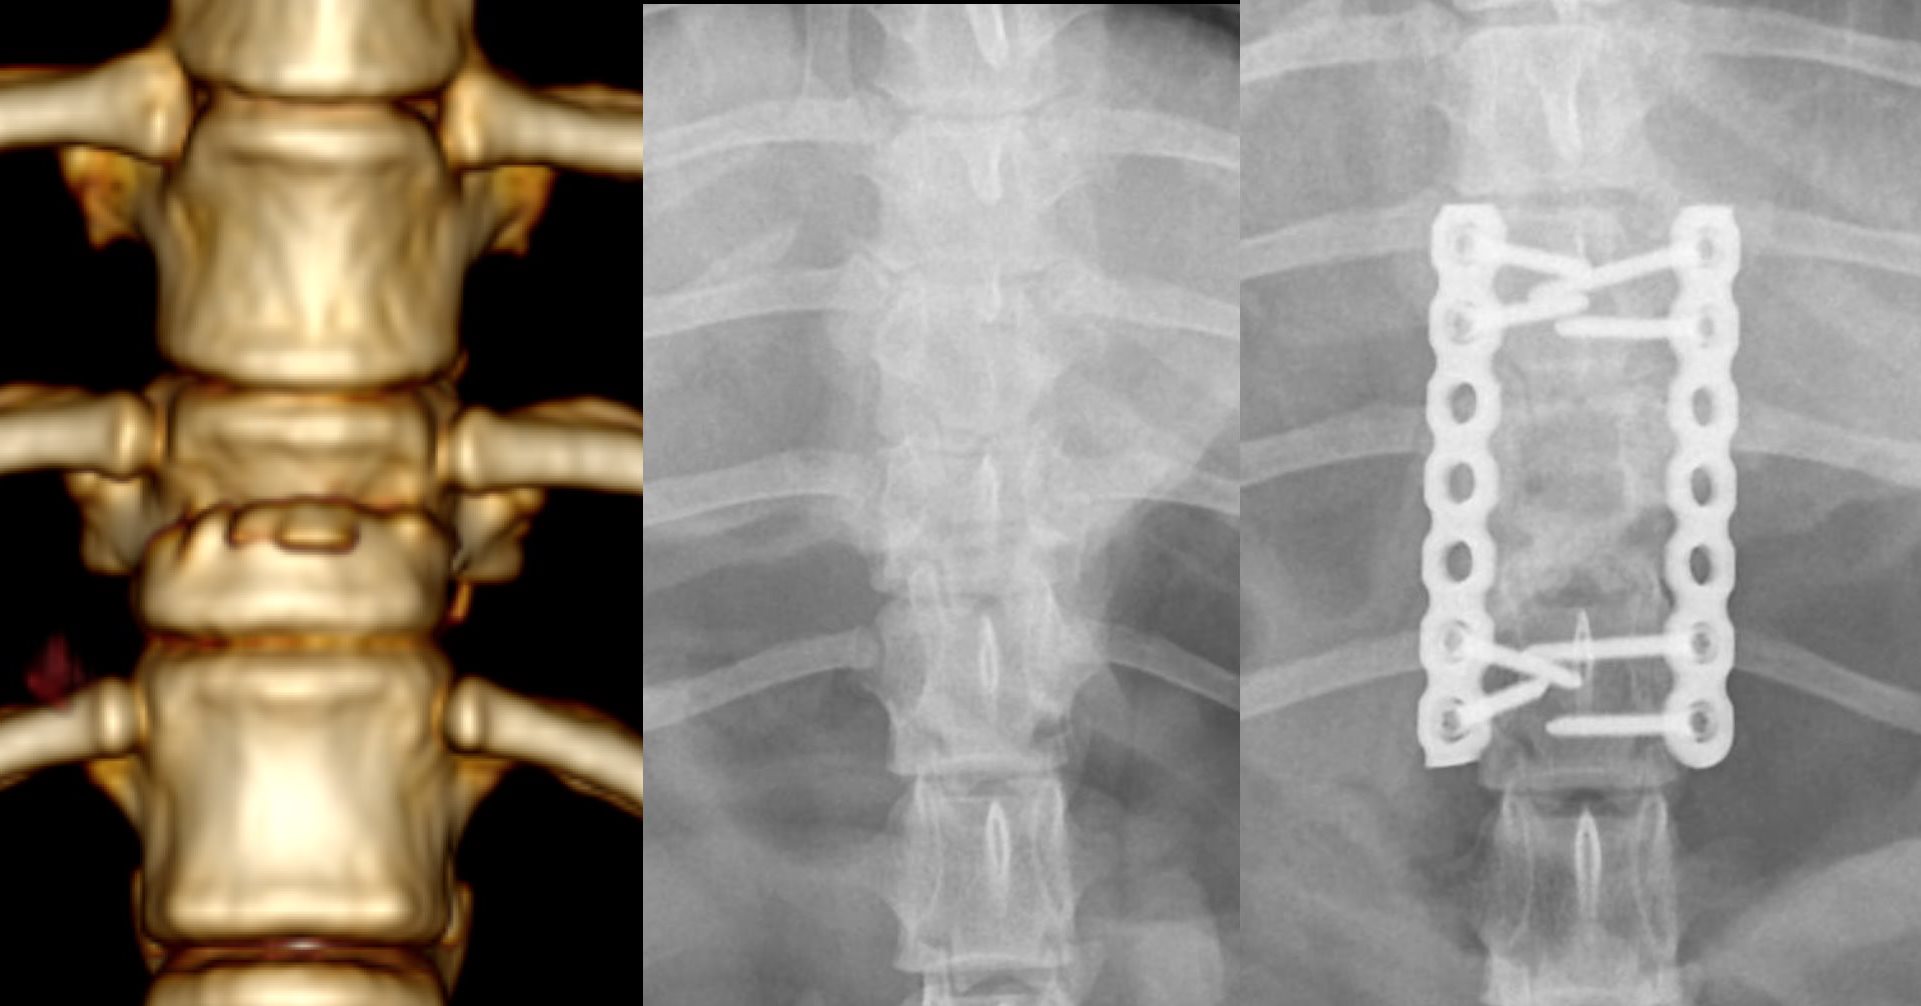

Começa a ser uma tradição a cirurgia de coluna de última hora!

Sou um felizardo porque tenho a melhor equipa do mundo!

Obrigado equipa Bonematrix!

Feliz ano novo a todos.... para o ano há mais!!!